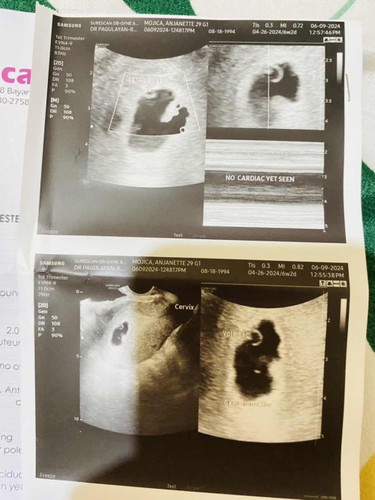

GESTATIONAL SAC IRREGULAR SHAPED

Hi tnong ko lang po if may same experience po dito. first Tvs ko po bahay bata pa lang nkita 6 wks umulit ako at yan nga sa picture may yolk sac and fetal pole na pero wala pa heartbeat. Ngworry lang ako sa shape ng GS ko parang hndi normal. Thankyou po